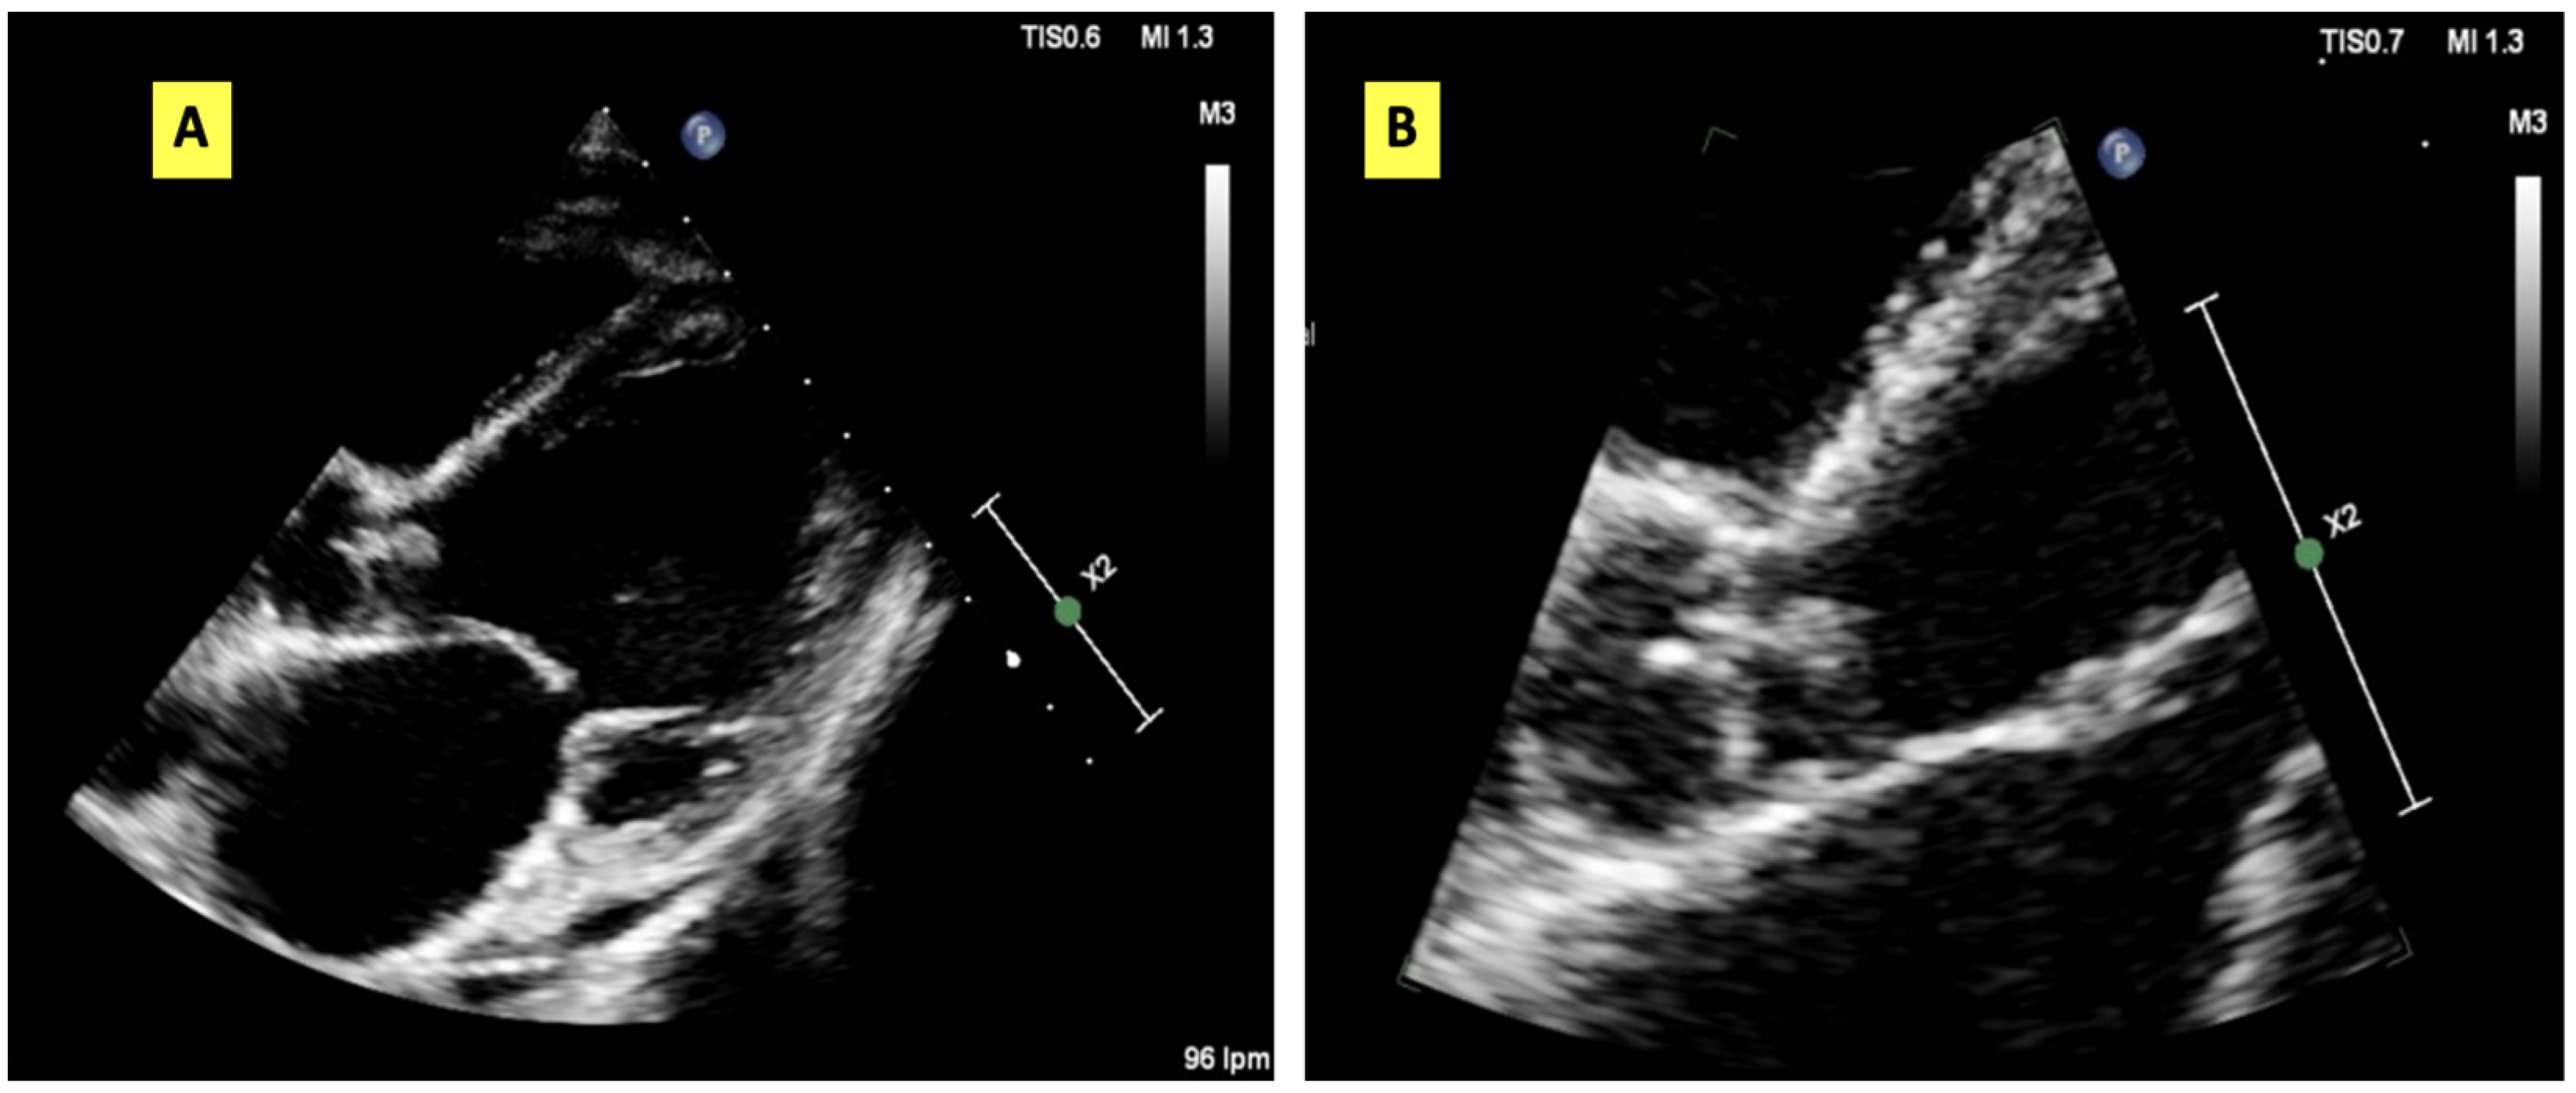

2. Case Presentation